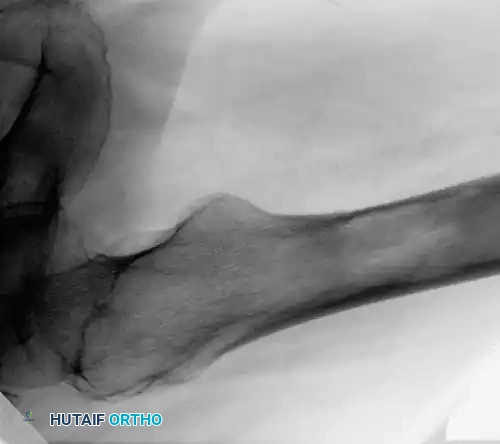

Fig. 22-24: (A, B) Anteroposterior and lateral radiographs of the proximal femur in an 82-year-old man with metastatic kidney cancer revealing multiple lytic lesions. Prophylactic fixation was canceled due to medical instability. (C) Radiograph several weeks later showing a completed pathological fracture. Surgery is now exponentially more difficult, and the patient has suffered severe morbidity.